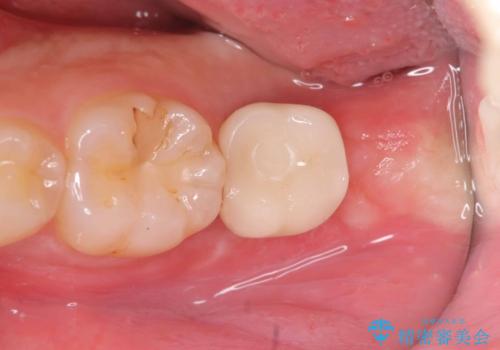

インプラントの上部構造(被せ物)には「スクリュータイプ」と「セメントタイプ」の2種類がありますが、セメントタイプは残留セメントが原因となり、インプラント周囲炎を引き起こす可能性があります。

そのため、当院では基本的に清掃性やメンテナンス性に優れたスクリュータイプを採用しております。